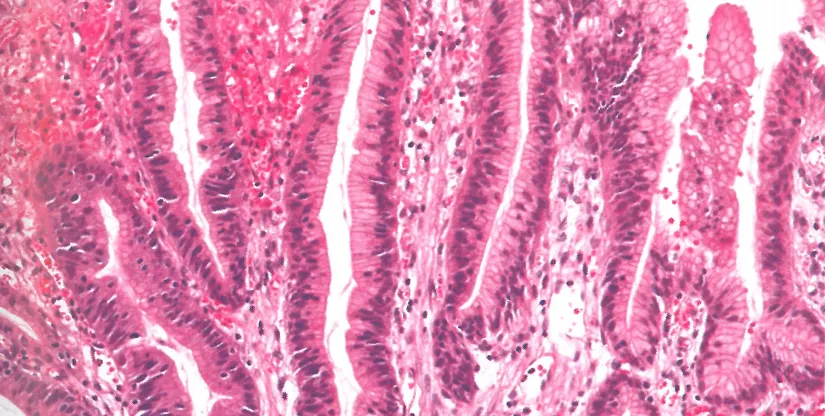

肠型高级别异型增生:肠型分化高柱状细胞核排列紊乱

胃型高级别异型增生:高柱状细胞核排列紊乱。

p53过表达